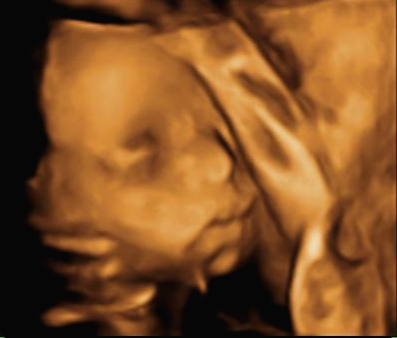

24주 차에 다시 사설로 초음파 검사를 받으러 갔는데 초음파를 보시더니 정밀 초음파 검사 때 성별 딸이 었냐 아들이 었냐 물어보시길래 딸이라고 말을 하니 미안하다고 지금 보니 딸이라고 하길래 이때는 정밀 초음파 검사 후 한 달 뒤여서 상관없다고 ㅋㅋㅋㅋㅋ 아들인지 딸인지 뭐가 중요하냐고 아이만 건강하면 된다고 하니 ㅎㅎ 그때서야 웃으시더라고요 ㅎㅎ 많이 미안했던 모양... 워낙 아이 건강상태를 꼼꼼하게 잘 봐주시고 만족할만하게 아이 얼굴 초음파 사진을 찍어주셔서 다 용서가 됐어요 ㅎㅎ

내 뱃속에 이렇게 사랑스러운 아이가 있다니 >. < 이렇게 이쁜 아이를 보면 성별반전은 중요하지 않아요~

입체 초음파 사진은 항상 만족스러워요! 사진 보면 벌써 태어난 아기처럼 어찌 이리 이목구비 뚜렷하고 아이 얼굴이 선명하게 잘 보이는지~ 제아이라 이렇게 사랑스러운 걸까요~? ㅋㅋㅋ